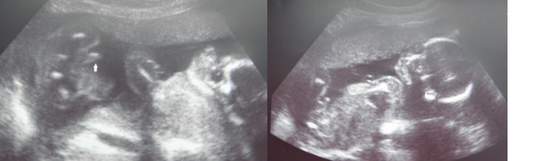

Która jeszcze mamusia w najblizszym czasie ma usg połówkowe,a jeszcze nie wie o płci? Dużo nas zostało? Chyba lukne na nasza listę